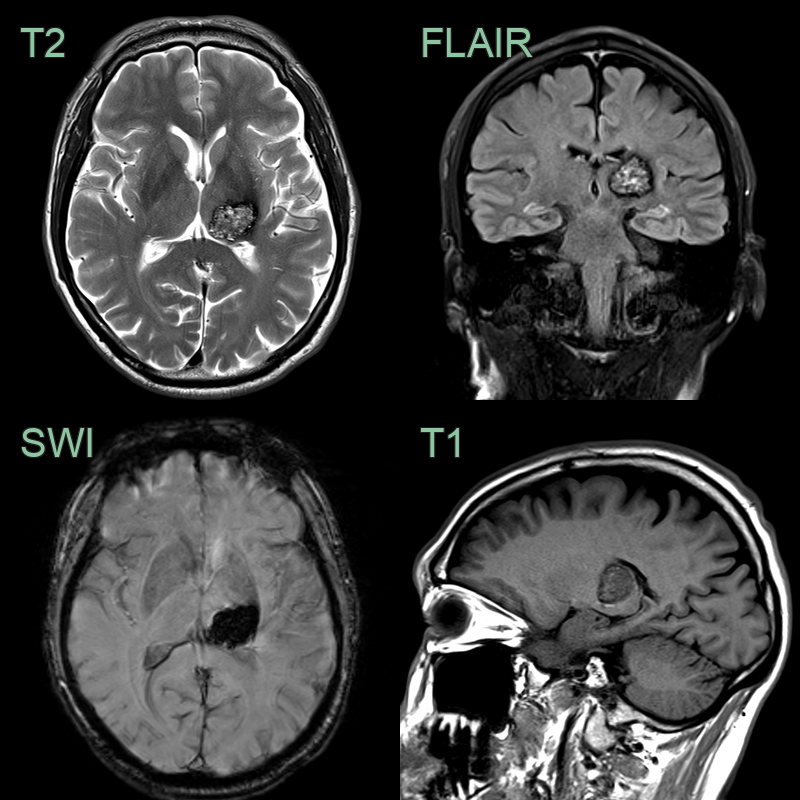

- T2 "Popcorn" or "mulberry" appearance with mixed signal intensity

- SWI Hypointense due to hemosiderin deposition and potentially calcification

- T1 Variable depending on presence or age of blood product

- ++T1+C++ Absent (or minimal) enhancement

- A 25-year-old patient was treated with whole brain and spine radiotherapy due to a disseminated medulloblastoma.

- An MRI performed 10 years after treatment, showed extensive radiation induced changes including hazy white matter hyperintensity, multiple cavernomas (red arrow), microhemorrhages and excessive mineralisation in the basal ganglia.

- The phase data from SWI showed mixed paramagnetic hemosiderin (black) and diamagnetic calcium (white).